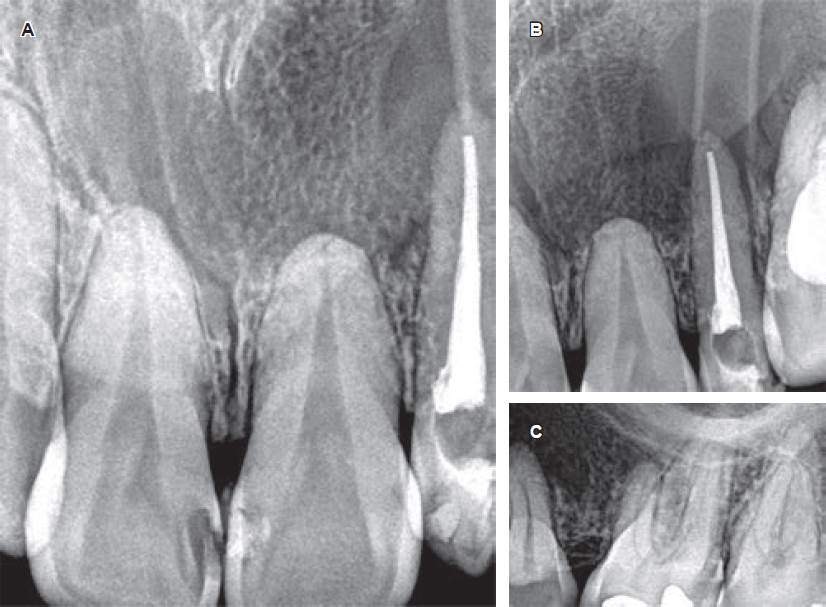

3) Seguimiento y controles: se realizaron controles clínicos y radiográficos mensuales, mientras la paciente seguía realizando los lavados mediante el tubo de drenaje ubicado ad hoc con el objetivo de llevar a cabo la técnica descompresiva. A los tres y seis meses de control, se observó la formación de trabéculas óseas (evidenciables en las radiografías intraorales de control) próximas a los límites anteroposteriores de la lesión quística (Figura 4).

Figura 4 Imágenes radiográficas periapicales de control. A-C) Imágenes radiográficas periapicales de control durante el seguimiento clínico del caso, observando la aposición de tejido óseo en las áreas periféricas del quiste, y reducción del tamaño de la lesión.